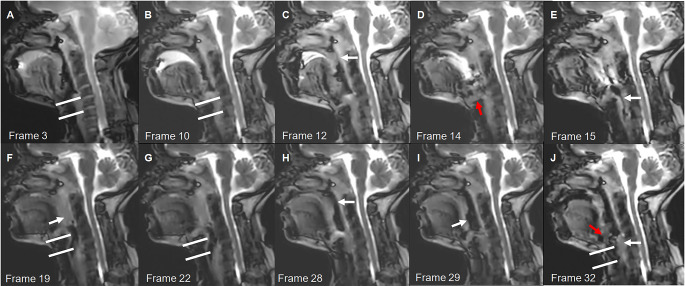

Cine magnetic resonance imaging (Cine-MRI) may evaluate the swallowing function and locations of patients with dysphagia, which requires very fast imaging speed. Compressed sensing is a technique that allows for faster MRI imaging by sampling fewer data points and reconstructing the image via optimization techniques, crucial for capturing the rapid movements involved in swallowing. This study aimed to analyze swallowing function and locations in patients with head and neck cancer and healthy individuals using Cine-MRI based on compressed sensing. This comparative study enrolled 36 patients with dysphagia and 10 healthy controls at the Department of Radiology, Yunnan Cancer Hospital between June 2020 and January 2021. Significant correlations were found between primary tumor location and Cine-MRI parameters, and between swallowing function and Cine-MRI parameters. The areas under the receiver operating characteristic curve for the combined Cine-MRI-related parameters in predicting mild and severe dysphagia were 0.806 (95% CI: 0.662-0.949). Cine-MRI with compressed sensing may identify swallowing function and abnormal stages of the physiologic swallowing process in patients with dysphagia after treatment.